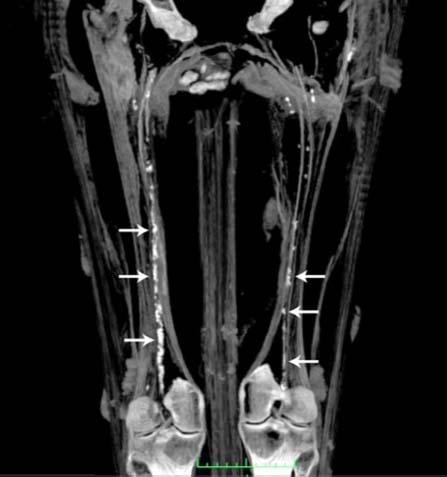

While atherosclerosis has been observed before in ancient Egyptians, this study found it to be more prevalent than previously thought. The interdisciplinary team performed whole body computerized tomography (CT) scans on 52 ancient Egyptian mummies to determine if atherosclerosis was present. Of the 44 with identifiable arteries or hearts, nearly half (45 percent) had calcifications either in the wall of an artery or along the course of an artery that are diagnostic of or highly suggestive of atherosclerosis. “Commonly, we think of coronary artery or heart disease as a consequence of modern lifestyles, mainly because it has increased in developing countries as they become more westernized,” said Gregory S. Thomas, M.D., MPH, clinical professor and director of nuclear cardiology education, University of California, Irvine and the study’s co-principal investigator.

“These data point to a missing link in our understanding of heart disease, and we may not be so different from our ancient ancestors.” Most of the atherosclerosis was found in the large arteries of the body, including the aorta in the abdomen. However, key smaller arteries were also involved. About 7 percent of the mummies had obstructions in the heart arteries, and 14 percent had blockages in the arteries to the brain, the carotid arteries, which is a leading cause of stroke in the present day. Researchers also found that, similar to now, advancing age was highly predictive of the presence and severity of atherosclerosis.

Thomas explains that the calcific atherosclerosis seen with CT scanning looks just like the atherosclerosis of today and appears in the same locations. While researchers could not determine the exact cause of death in these mummies, symptoms consistent with cardiac chest pain had been described in ancient Egyptian scrolls. In order to understand the lifestyles of ancient Egypt’s elite, the team of researchers worked with Egyptologists to review risk factors that might affect the health of the heart and arteries.